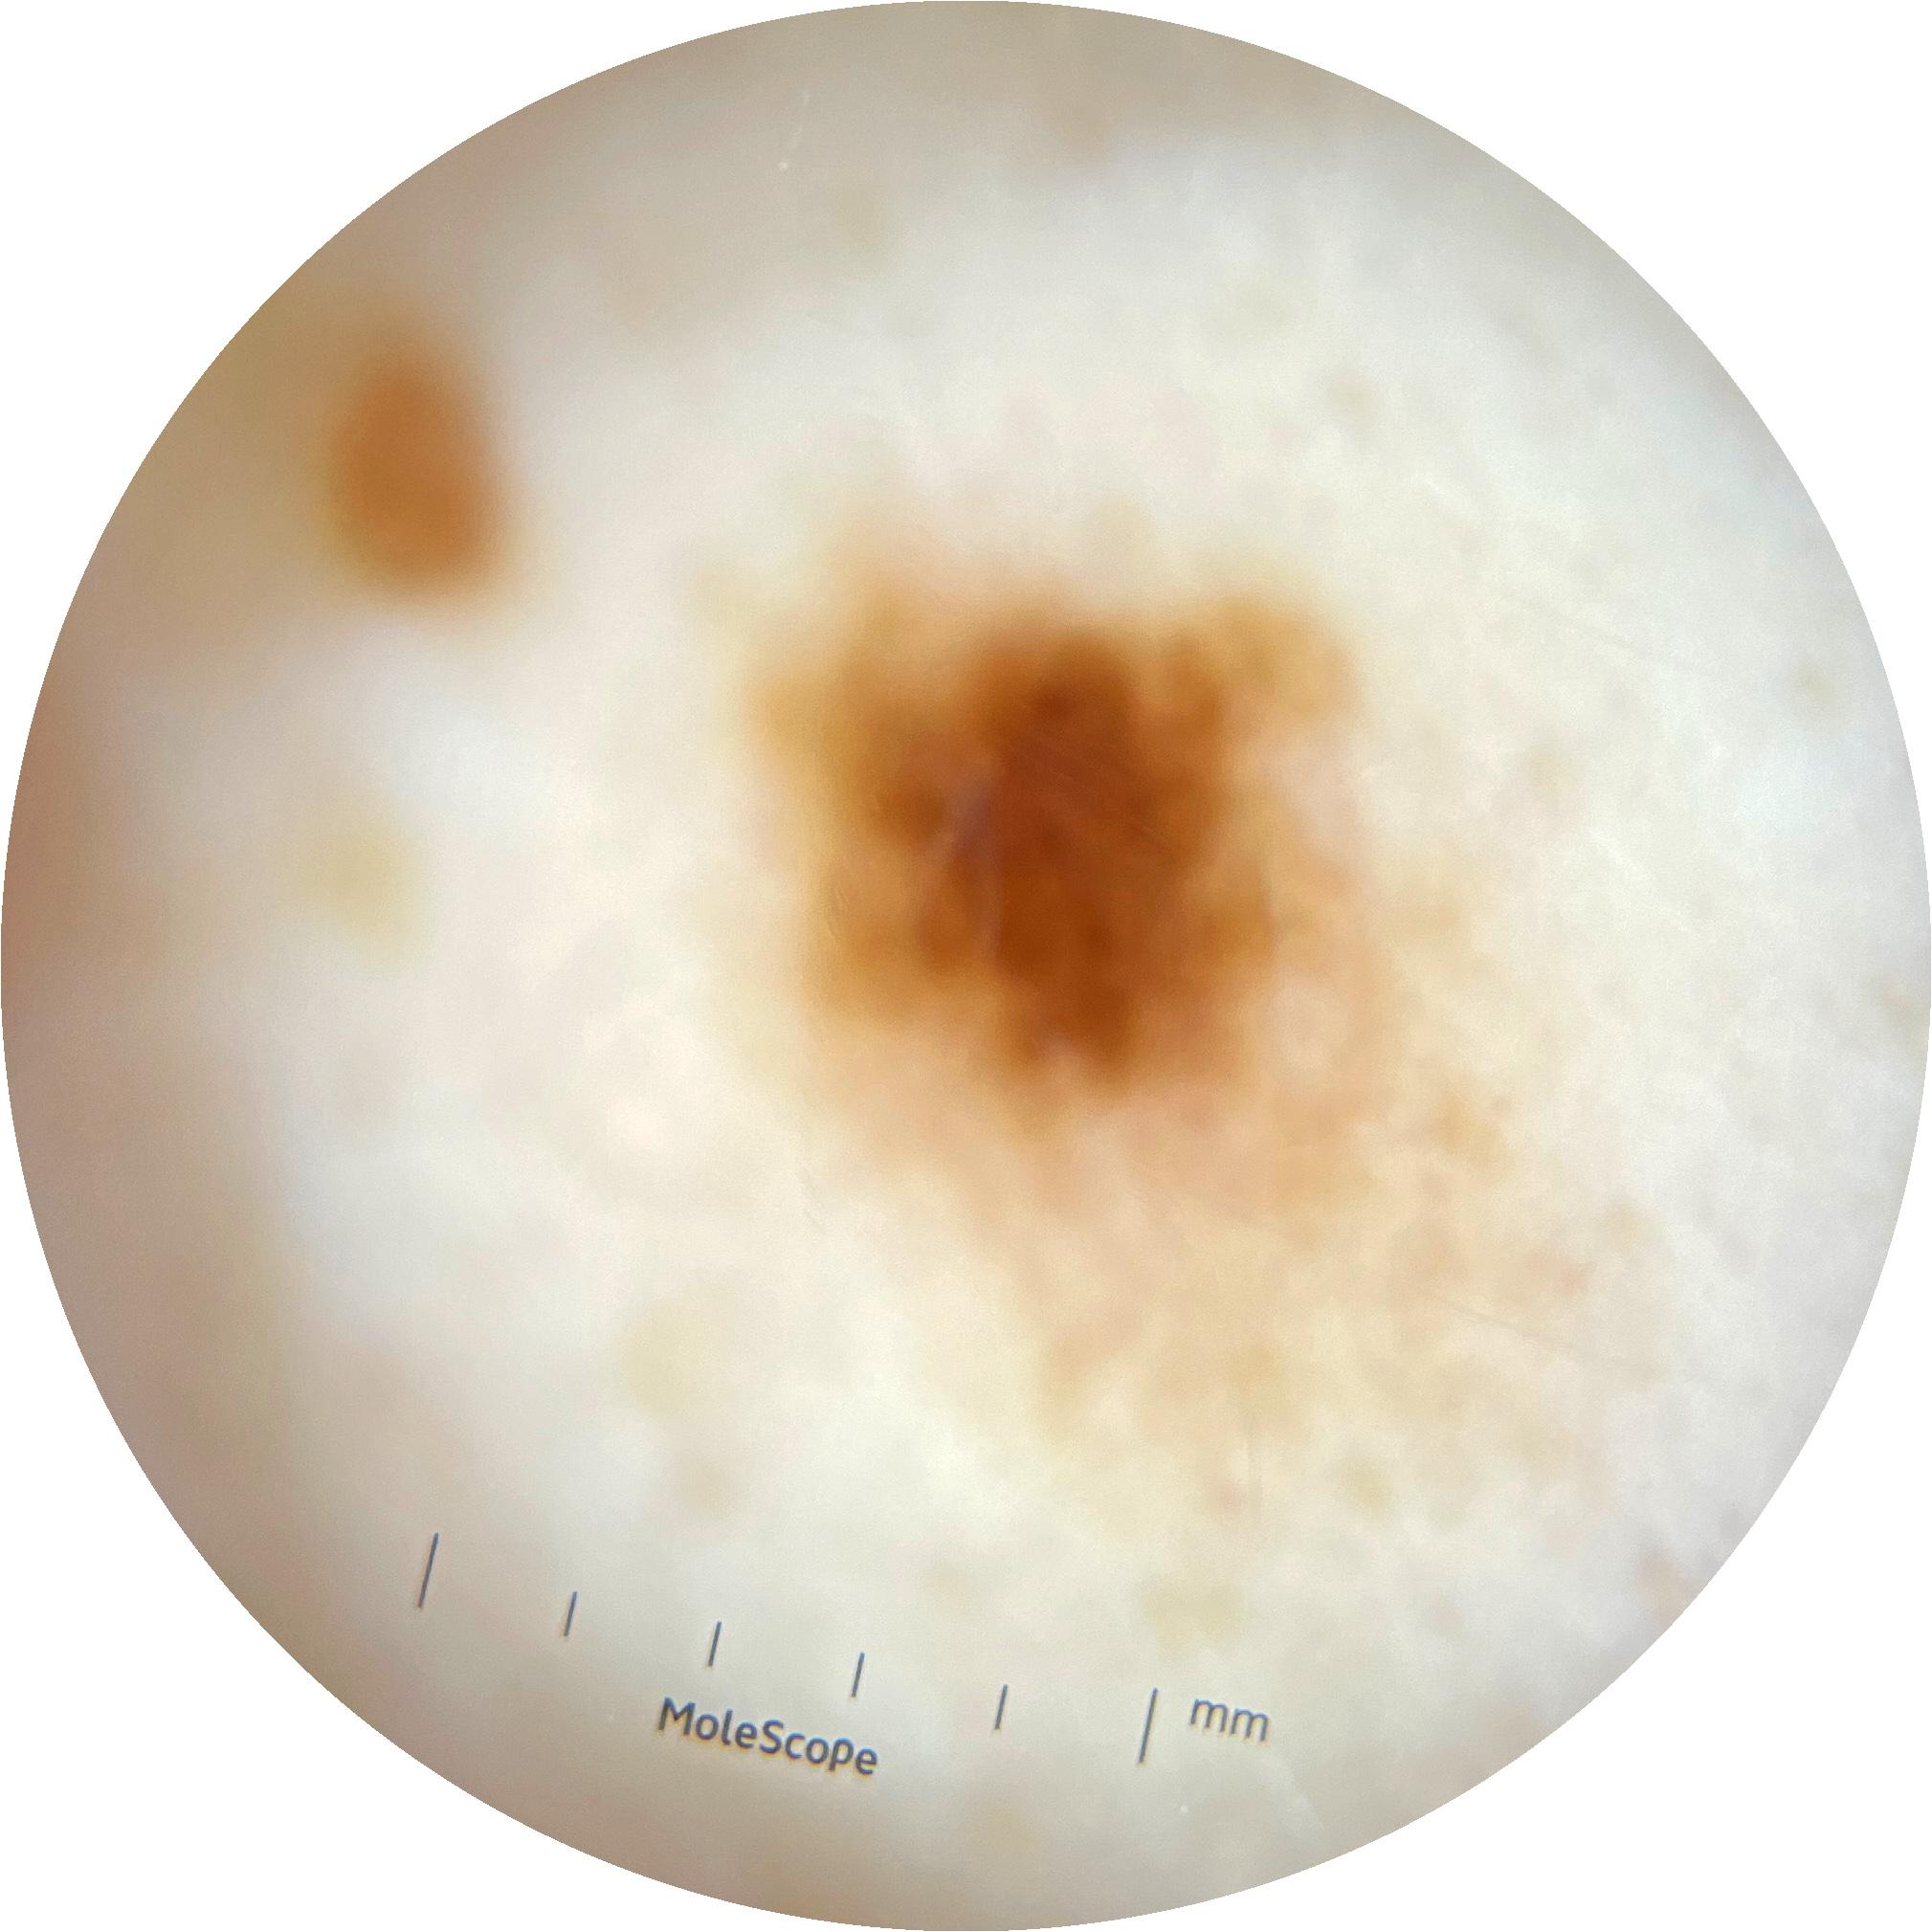

ISIC_0389414

2001 x 2001

IP_3403943

IL_4535151

acquisition_day 335

age_approx 60

anatom_site_1 Trunk

anatom_site_2 Anterior trunk

anatom_site_general anterior torso

diagnosis_1 Benign

diagnosis_confirm_type single image expert consensus

family_hx_mm True

image_type dermoscopic

personal_hx_mm True

sex female